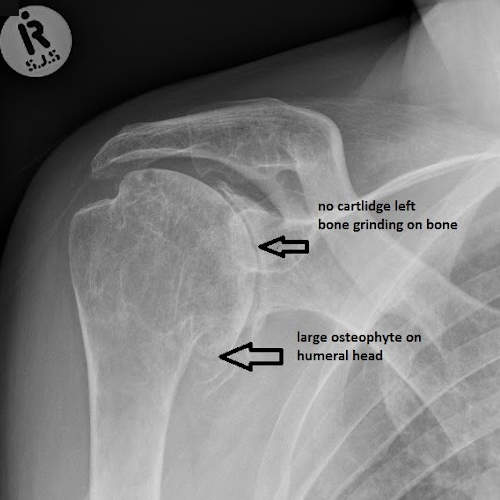

Shoulder Osteoarthritis

Goal: Preserve joint function

How: Progressive loading to improve bone density and maintain soft tissue support.

Surgical “shaving” of bone often no better than exercise for long-term impingement relief.

Total joint replacement for severe arthritis or irreparable cuff tears if conservative treatment fails.